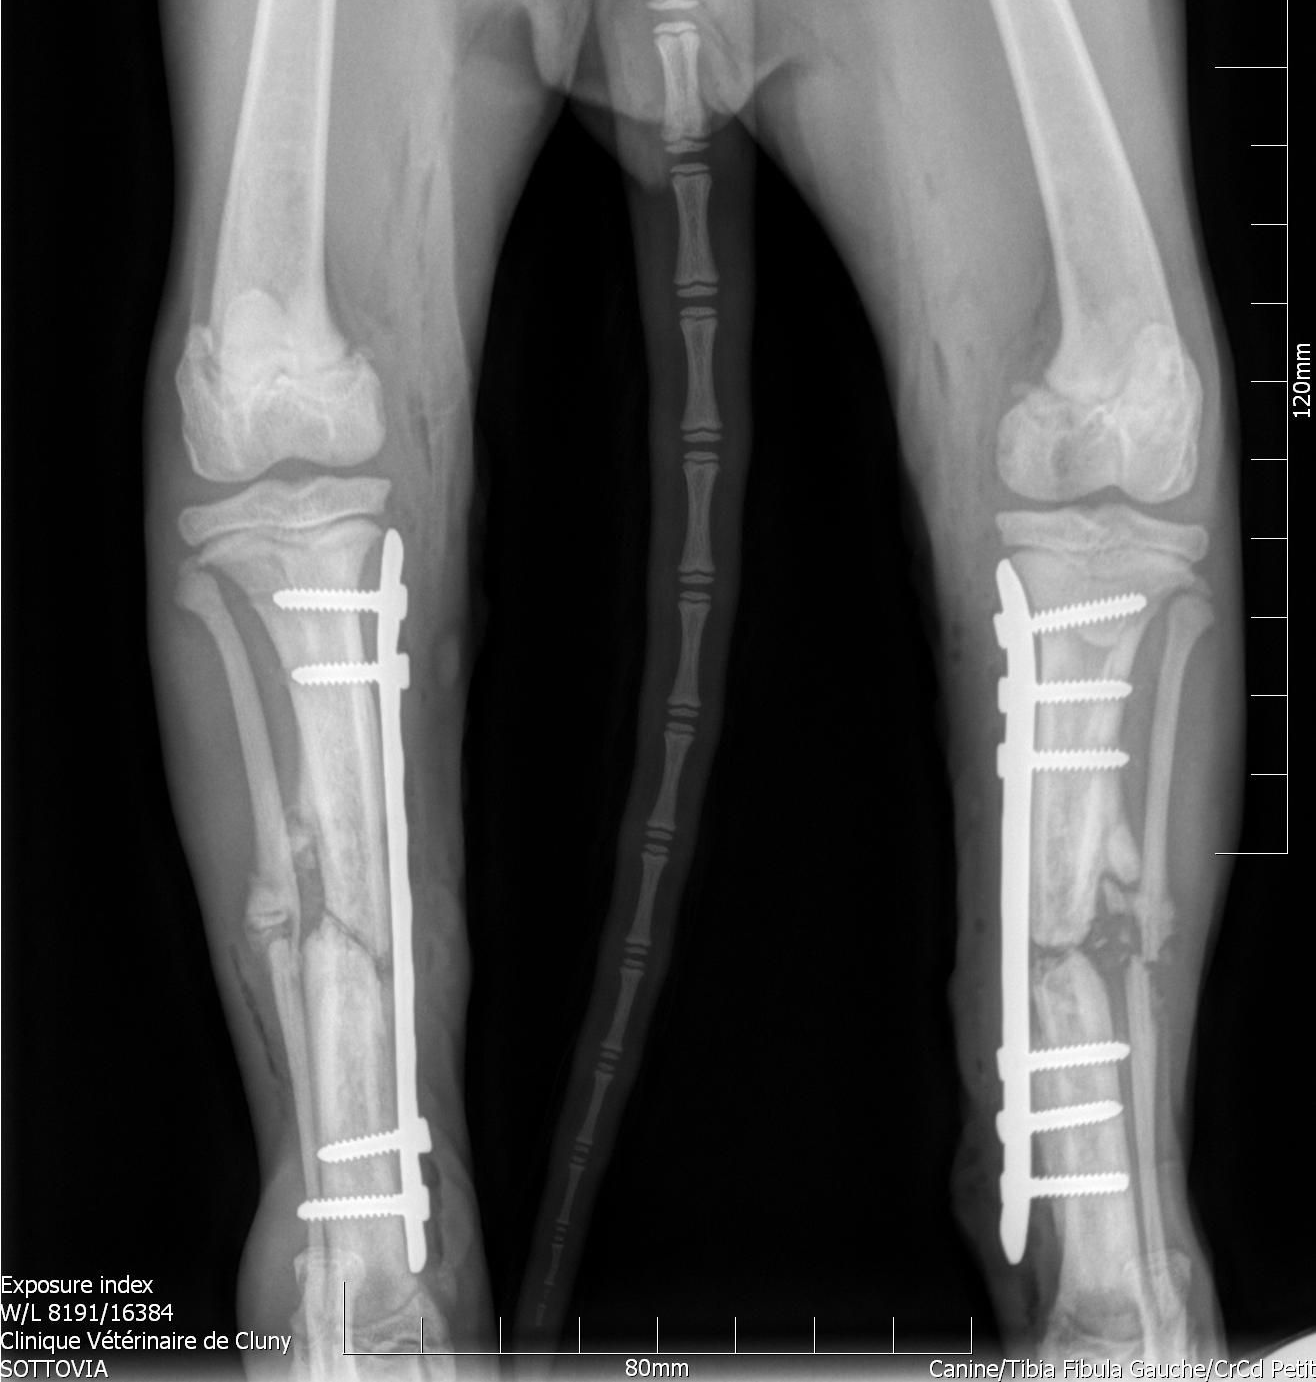

La chirurgie ostéo-articulaire consiste à corriger les atteintes osseuses comme les fractures et articulaires comme les ruptures des ligaments croisés.

Ces chirurgies sont réalisées par la Dr De Gryse qui est formée en chirurgie orthopédique, et qui continue de se mettre à niveau.

Notre vétérinaire commencera par effectuer des clichés radiographiques, afin de décider de la meilleure méthode chirurgicale à adopter.

Une fois la chirurgie réalisée, des nouveaux clichés seront réaliser pour s'assurer de la bonne mise en place du matériel orthopédique.

Un suivi médical vous sera proposer pour s'assurer de la meilleure rémission de votre animal, avec des conseils pour les soins à faire à la maison et vous impliquer dans le processus de guérison.